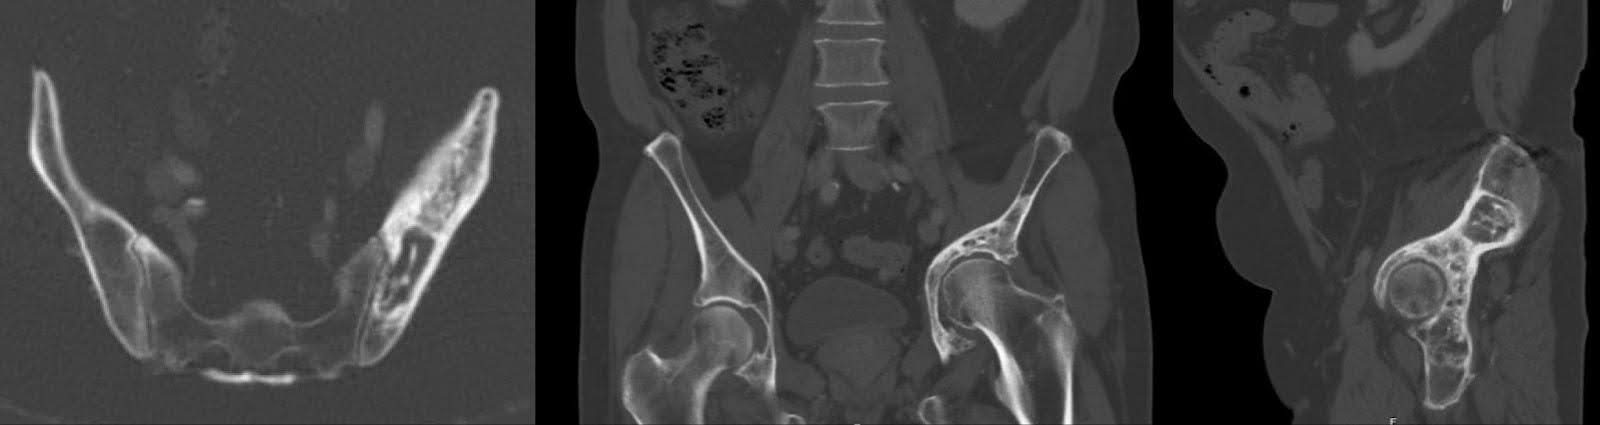

As radiografias subsequentes, realizadas três meses antes da cirurgia, não revelaram nenhuma alteração substantiva na aparência de lesões escleróticas e líticas mistas na hemipelve esquerda, de acordo com o linfoma tratado. Isso foi acompanhado por remodelamento acetabular e migração cranial do fêmur proximal, com alterações degenerativas na articulação do quadril esquerdo (Figura 1). Os achados da tomografia computadorizada (TC) alinharam-se aos radiografados, confirmando a patologia observada (Figura 2).

Figura 2. Incidências axial, coronal e sagital da TC da pelve três meses antes da cirurgia. Lesão mista esclerótica/lítica do acetábulo redemonstrando linfoma tratado. Colapso do teto acetabular e migração do fêmur proximal para a área supra-acetabular com protrusão.